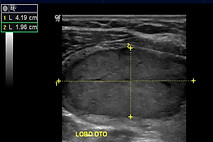

Se o seu médico lhe solicitar uma citologia (imagem ao lado), saiba desde já que é um exame simples e pouco doloroso. A agulha utilizada é igual à que se usa para administrar vacinas e a punção dura apenas alguns segundos, podendo as pessoas retomar as suas atividades normais posteriormente.